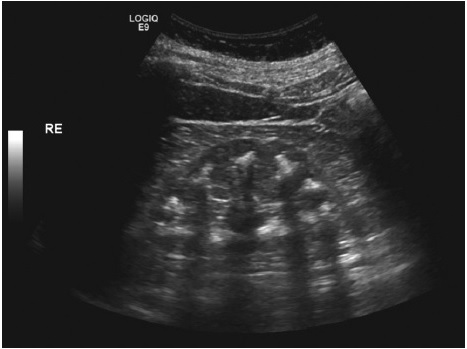

De acordo com Trindade, a síndrome de Bartter é uma doença que acomete uma parte dos rins ocasionando excessiva perda de potássio, sódio e cálcio, dentre outros elementos. Em alguns casos, pode haver evolução para surdez e, se não detectada em tempo, a criança acometida pela síndrome pode ter atraso no crescimento, déficit cognitivo e até chegar a óbito.

Por sua vez, a síndrome Unha-patela ocasiona sangramento na urina e insuficiência renal crônica na vida adulta. O gene implicado nesta doença também está sendo relacionado, em vários estudos, ao câncer de mama e a alterações oculares.